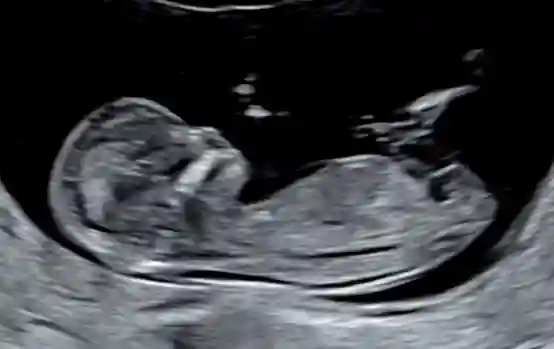

高龄二胎NT秒过~👀 供卵婴儿多少钱

#产检 #孕期

#肚子里的宝宝 #NT #二胎 #接好孕 #胎宝宝在肚子里的状态 #怀孕#胎梦 #胎梦玄学